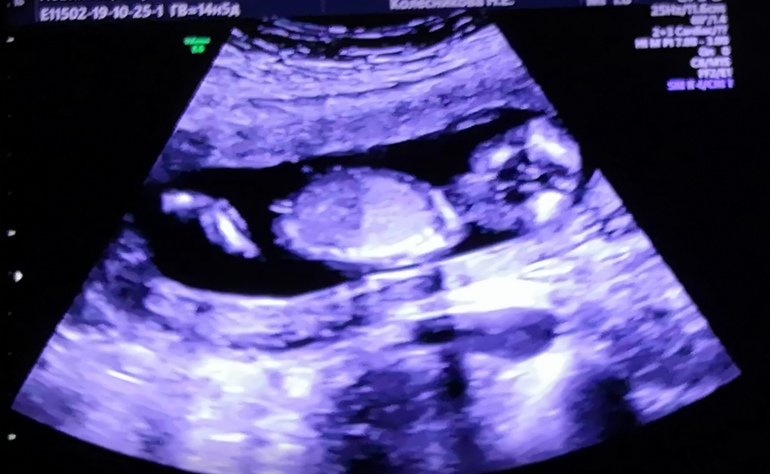

Пол ребёнка (14,5недель)

Пол малышаДевочки, об'ясните мне не долугой, это пуповина или нет на 1 фото.? А то мне 2 раза говорили девочка, а сегодня предположили мальчика😔. Теперь ждём 2 скрининг. Эхх😔

Вроде не пуповина,а бугорок прямой на девочку 🤷🏻♀️ У моего пацана торчал сильнее и мне врач сказал,что это не пуповина 🤪

Ну по фото и по этому способу девочка. Но не всегда верно определяют, на первом скрининге можно сделать только предположение, но никак не сказать точно.

девочка) писюн не так торчит, вверх) а у вашего малышастика в сторону

Лично я, практически уверена, что это пуповина). Ну и визуально, очень лялька на девочку похожа, ну а если мальчик, то уж очень аккуратный мальчишка). Пусть будет девочка все таки